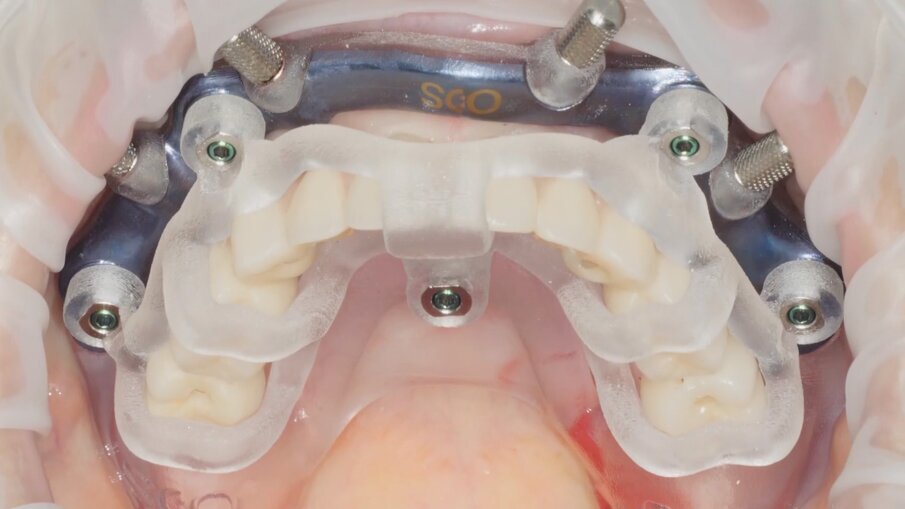

Veniamo quindi al posizionamento della protesi mediante carrier, a sua volta ancorato agli stessi punti di fissaggio della dima base. È significativo osservare come la stabilizzazione della sola vite palatale consenta l’allineamento perfetto tra i sistemi di fissaggio (Fig. 22), mentre il dettaglio mostrato in Fig. 24 illustra efficacemente come prima della cementazione della protesi l’accoppiamento e la centratura del foro protesico appaiano perfetti, confermando quindi come l’obiettivo di alloggiamento della protesi nella sede prestabilita sia stato colto. Per la fase di cementazione con cemento duale si è prestata attenzione alla realizzazione di un foro aggiuntivo per permettere al materiale di raggiungere gli abutment. I fori di accesso alle viti vengono tappati con filo di teflon (Figg. 25, 26) ed è a questo punto possibile andare a fissare la protesi e rimuovere il sistema carrier (Fig. 27). Lasciamo la dima in posizione, così che nell’eventualità in cui un abutment non dovesse essere stato cementato correttamente, ci riserviamo la possibilità di riprendere il posizionamento strategico dell’intero sistema Pcube, intercettando possibili impedimenti alle manovre di finalizzazione del caso.

Nella fase di controllo finale possiamo apprezzare come i rapporti di intercuspidazione programmati siano stati perfettamente rispettati (Fig. 28), senza necessità di ricorrere a procedure di auto-centratura della protesi, grazie ad una attenta pianificazione digitale. Eseguiamo una scansione con scan abutment in posizione prima di procedere con la rimozione della dima base e il fissaggio della protesi (Figg. 29-31). Controlliamo le possibilità di mantenimento igienico tenendo conto che, trattandosi di un intervento flapless, non abbiamo le problematiche legate alla gestione di una linea di incisione (Fig. 32). La Fig. 33 mostra la corretta guarigione dei tessuti quindici giorni dopo il trattamento. Eseguiamo un controllo radiografico mirato a verificare il corretto alloggiamento di tutti gli impianti e della protesi (Fig. 33), dove possiamo vedere la struttura di rinforzo in fibra di vetro.